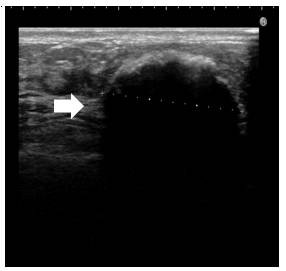

最後のパターンは、一番 硬くなった 石灰化型 のしこりについて説明します。

この型は、しこりを長い期間放置し、壊死した脂肪を包んだ膜が、卵の殻のように、カチカチになった型です。

摘出したしこりです。